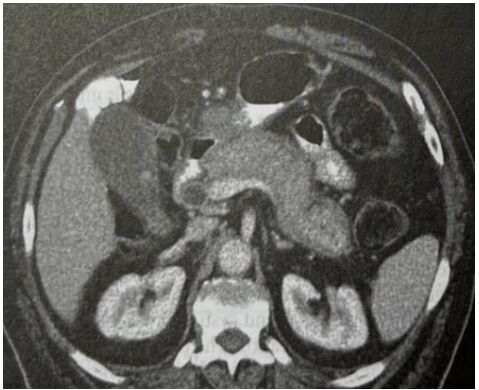

4. 病人是位29歲男性電子工程師派駐中國深圳,三個星期來,時有間歇性發燒及逐漸性呼吸困難,先在深圳 門診求醫,初以為一般感冒治療,後以支氣管炎診斷治療罔效,乃急回台灣求醫。經檢查,意識: E4M6V5; BP: 122/75 mmHg; PR: 116/min; RR: 21/min; Temperature: 37.6℃; SPO2: 94%(room air) 頸靜脈不怒張,未有貧血,胸部呈現瀰漫性濁音,心臟擴大,有Grade III/VI Diastolic murmurs at left upper sternal border,無肝脾腫大,無腹水。皮膚未有紅腫或出血斑點。2016/12/23心電圖及胸部X光如 圖。其血液、尿液及生化如次:Hemograms: WBC, 13.54(k/uL); RBC, 4.74(M/uL); Hb, 13.0 (gm%); HCT,40.2(%); MCV, 84.8 (fL); MCH,27.4(pg); Platelet,329 (k/uL); Seg, 81.5(%); Eos, 0.2(%)。尿檢: 正常。請 問這位年青病人的最可能診斷是: